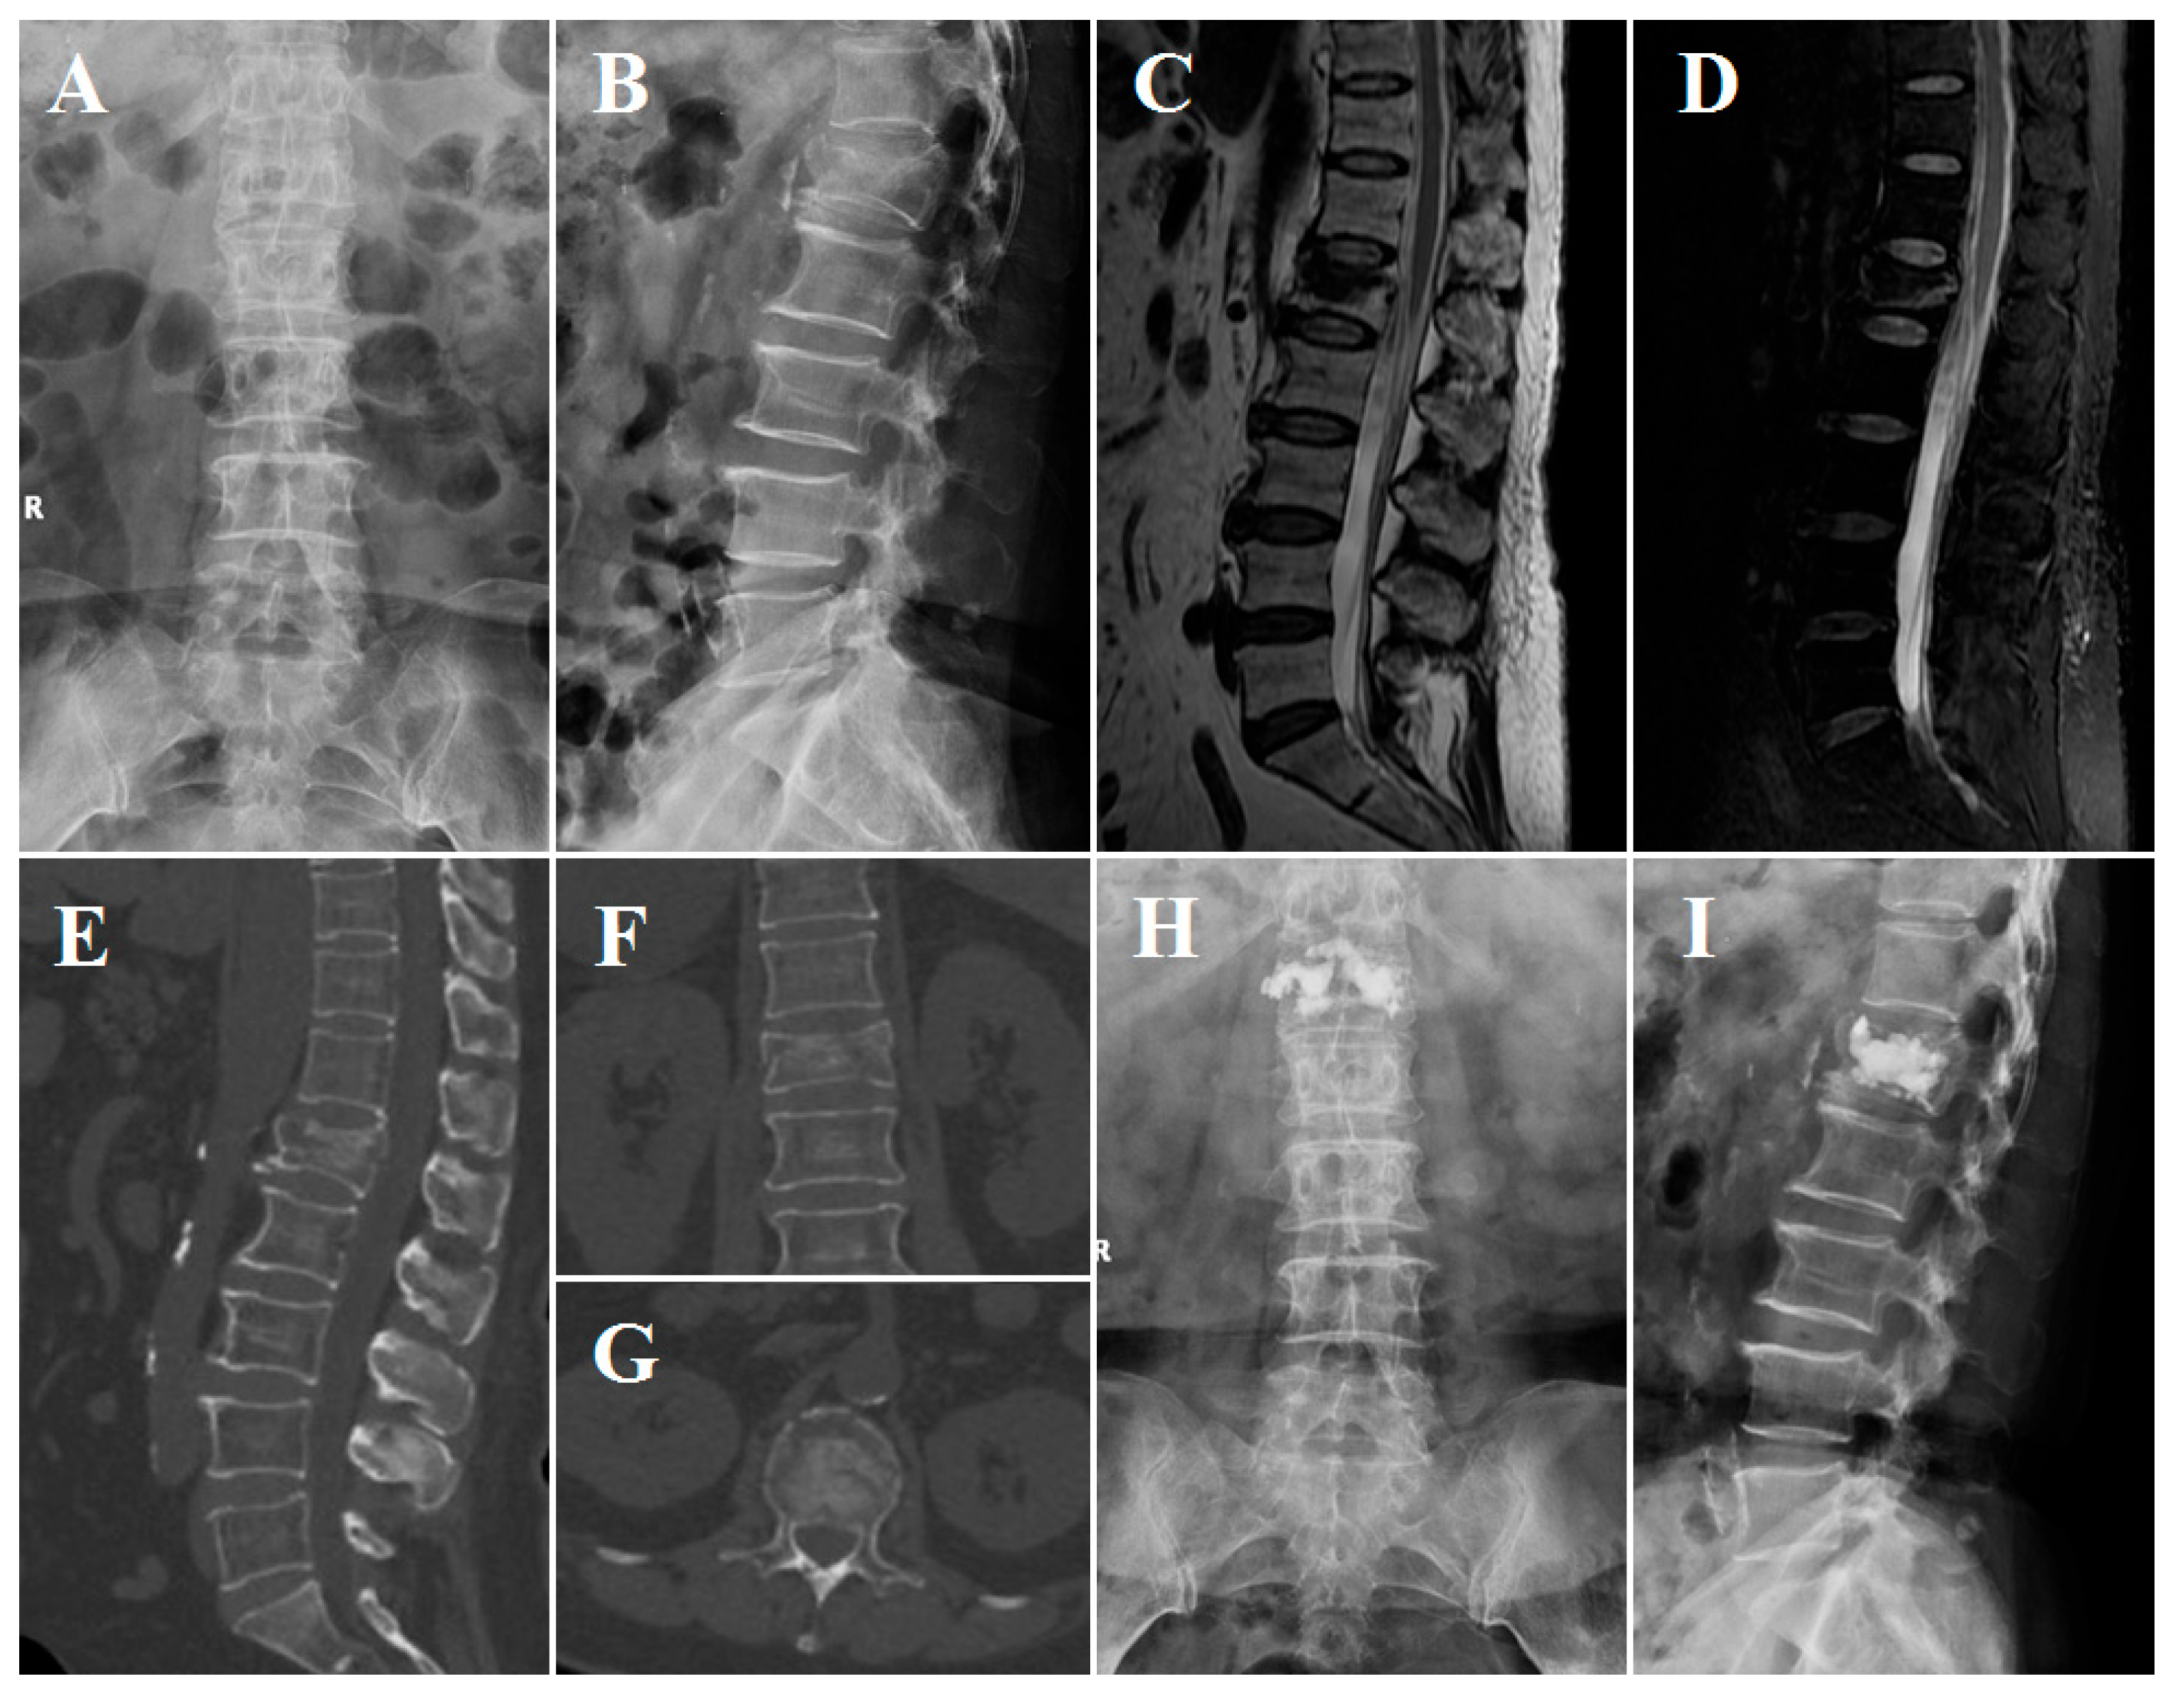

Figure 4.

Imaging obtained from the patient described above. (A–D) Preoperative X-rays and MRI. (E–G) Preoperative CT showing fissures in the lateral and upper endplates of the fractured vertebral body. (H,I) Postoperative lumbar X-rays obtained one day after PKP.